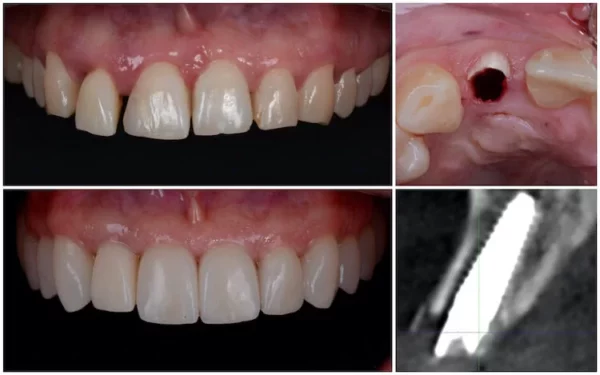

Amennyiben csak részlegesen hiányoznak fogak és azokat fogimplantátumokkal helyettesítettük, akkor rövidebb hidak készülnek, lehetőség szerint szintén csavarrögzítéssel. Előfordul, hogy csupán egyetlen fog hiányzik és annak helyére kerül beültetésre fogimplantátum. Ha ez a hiányzó fog a mosolyzónában helyezkedik el, akkor kiemelt és kritikus fontosságú a fogimplantátumra készülő fogpótlás természetes megjelenése.

Ez a feladat speciális felkészültséget igényel orvosi és fogtechnikusi oldalról egyaránt. Ilyenkor különös tekintettel kell lenni a fogíny lefutására és annak a természetes szomszédos fogakhoz való kialakítására. Bodrogi doktor nemzetközi előadásainak fő témája az esztétikai zóna ellátása különböző fogimplantációs megoldásokkal. Azonban az esztétika mellett a fogsorzáródás (harapás) optimalizálásán keresztül a helyes funkció kialakítása is kiemelt fontosságú a fogimplantációs beavatkozások kapcsán.

Dr. Bodrogi a UCLA Master Program in Implantology keretében sajátította el az azonnali, foghúzást követő fogimplantátumbehelyezési technikákat, mellyel megkímélhető a páciens a többszöri sebészi beavatkozástól és az indokolatlan csontveszteségtől (melyet később csak csontpótlással lehet kompenzálni). Így egységnyi gyógyulási idő alatt regenerálódik a húzás helye és gyógyul a csont a fogimplantátum körül.

A legtöbb esetben az azonnali fogimplantátum beültetéseknél szükség van egyidejű mérsékelt csontpótlásra is, hogy mind esztétikailag, mind funkcionálisan a legmagasabb értékű végeredmény születhessen. Ennél a beavatkozásnál is rutinszerűen alkalmazzuk a PRF technikát, hogy a centrifuga által kinyert koncentrátum a páciens saját növekedési faktorainak segítségével serkentse elő a gyógyulási folyamatot.

A legtöbb esetben lehetőség nyílik a fogimplantátum azonnali ideiglenes fogpótlással való ellátására is. Sajnos még csak kevesen ismerik és még kevesebben alkalmazzák ezt a technikát, Bodrogi doktor rendszeresen tart előadásokat és közöl publikációkat ebben a témában. Tagja egy nemzetközi kutatócsoportnak is, ahol egyre nagyobb számban publikálnak eseteket, közölnek eredményeket, tartanak képzéseket és fejlesztik magát a módszert is, hogy minél szélesebb körben váljon ismertté világszerte.

Azonnali ideiglenes pótlás készítésére akkor nyílhat lehetőség, amennyiben a fogimplantátum beültetése a tervezett módon, a megfelelő helyre és speciális felszíni kialakítással történt. A beültetés folyamatának végén megmérjük a fogimplantátum úgynevezett primer stabilitását, vagyis azt, hogy mennyire erősen rögzül az a csontban közvetlenül a műtét után. Erre egy felkészült rendelőben rendelkezésre áll egy ISQ mérőkészülék.

Amennyiben a mért stabilitás elér egy bizonyos mértéket, akkor lehet a fogimplantátumot ellátni azonnali ideiglenes pótlással. A SmileCenterben az esztétikai zóna fogimplantációs beavatkozásai során minden esetben törekszünk az azonnali ideiglenes ellátásra a gyorsabb gyógyulás és a tökéletes ínyesztétikai létrehozása miatt.